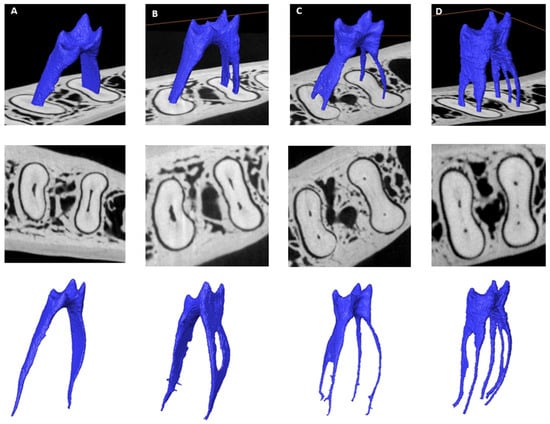

3.3. Number of Canals per Root

3.4. Chamber Canals